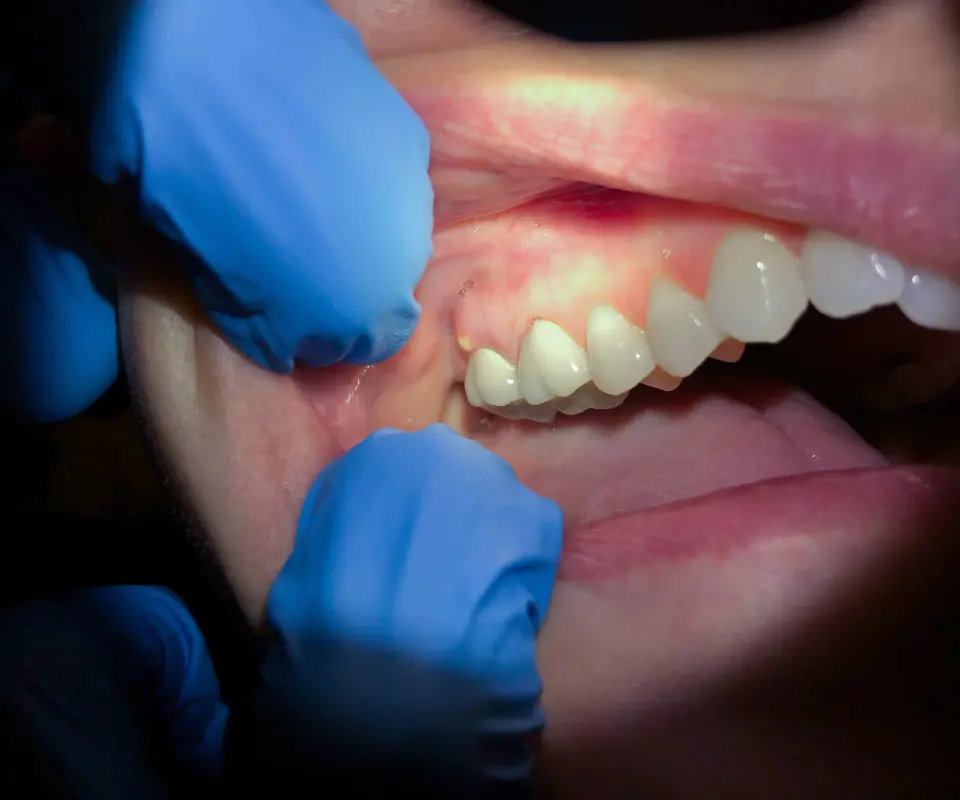

Wisdom Tooth Complications

Swollen jaw after toothache or from impacted wisdom teeth is very common. Conditions like pericoronitis can cause the surrounding gum and jaw area to swell if not treated in time.